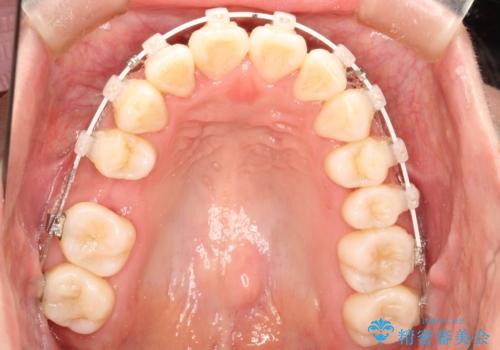

- 上の前歯が出てて、前歯で咬めないとのことで来院されました。

上顎の歯を1本抜歯して、前歯のガタガタと、前方に出ているのを改善する計画としました。

上下の前歯の距離が近くなり、前歯で咬みやすくなり、審美的にも改善できました。